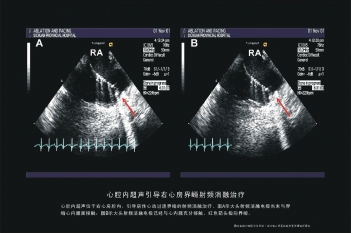

心耳起搏

希氏束起搏电极置放